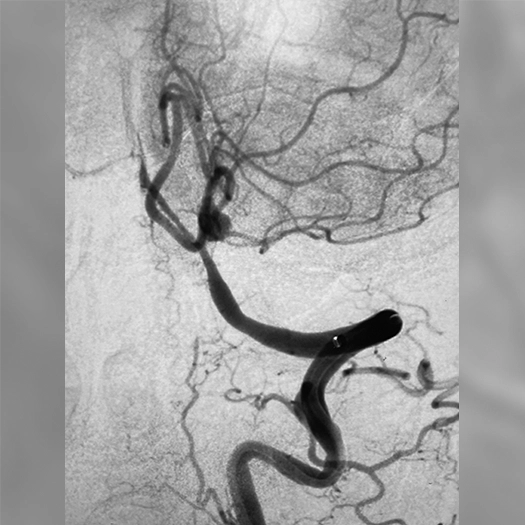

angiogram of an embolization coil place in an aneurysm

15 mm ICA terminus aneurysm coiled with PC400 and PAC400, 46% PD

Aneurysm

• PC400: optimized for aneurysm embolization

• Offered large volume with .020″ platform

• Supported by BENCHMARK family for stable access